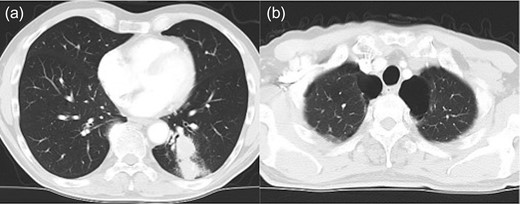

A 69-year-old man presented to our department for the treatment of left lower lobe lung cancer (adenocarcinoma, cT2aN0M0 stage IB) (Fig. 1A). He was previously a heavy smoker (Brinkman index 720); he did not take anticoagulants or antiplatelet drugs, as the coagulation tests revealed no abnormalities. Preoperative chest computed tomography revealed that pulmonary emphysema was dominant in both the upper lobes, and multiple bullae were found in the apex of the lung (Fig. 1B).

Chest computed tomography shows lung cancer in the left lower lobe of the lung (a) and an emphysematous lung with bullae in the lung apex, bilaterally (b).